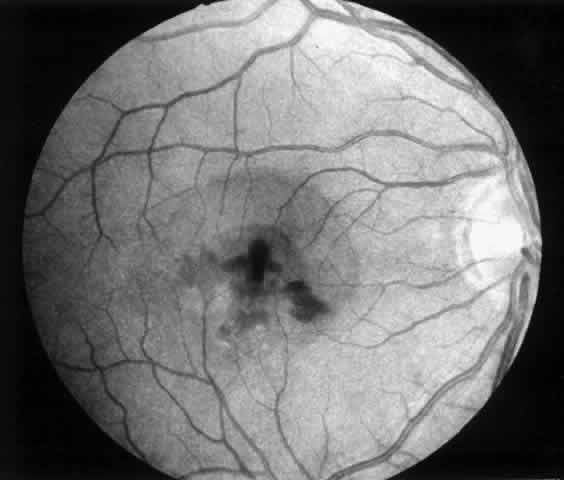

| Patients are examined 1 and 7 to 10 days after surgery to verify that intraocular pressure is acceptable, the retina remains attached, and no infection occurs. Three weeks after surgery, the view is usually adequate for assessment of the presence or absence of subfoveal RPE. Occasionally, residual subretinal blood will obscure the underlying tissues for a longer period of time. Within the first month, angiography is repeated to evaluate for recurrence of neovascularization. Not uncommonly, the site of the original choroidal ingrowth stalk demonstrates recurrent neovascularization. Often this site is not subfoveal and therefore slit lamp laser photocoagulation can be employed to ablate the recurrence. Given the fact that membranes recur in approximately one third of cases within 6 months, close follow-up is essential. |

MEMBRANES ANTERIOR TO RETINAL PIGMENT EPITHELIUM At the present time, we advise surgical extraction of a membrane only if the membrane appears to lie anterior to the RPE. In some cases, this is an easy determination to make preoperatively; in others, it is difficult. We study the macula with stereoscopic viewing at the slit lamp through a 60- or 78-diopter lens or with a contact lens. We also obtain color, stereo, 2× magnified views of the macula for subsequent review. The findings on clinical examination that suggest an anterior location may include the following:

Angiographic findings consistent with membranes anterior to the RPE include the following: